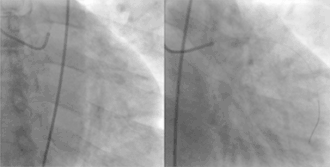

| Coronary arteries providing blood to the heart. The blood vessels originate from the aorta and surround the heart. | |

![]() Showing the coronary arteries that are subject to narrowing - resulting in reduced blood supply to the cardiac muscle. | |